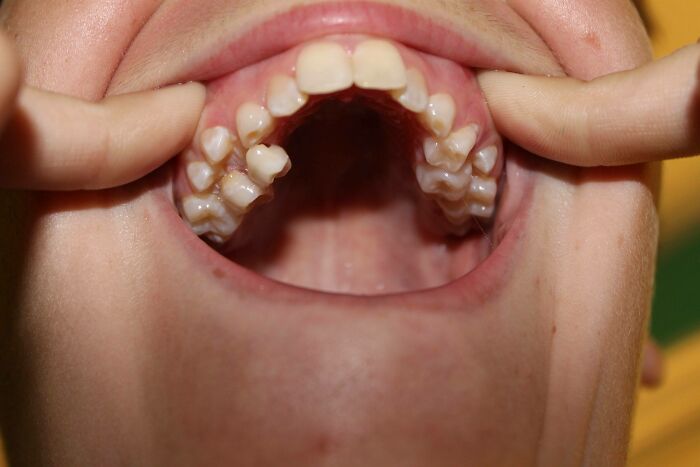

#11

I didn’t know him, but one time I was helping a customer at a grocery store I worked at and he threw his head back and laughed, and I saw he had two rows of top teeth.

wtfbenlol:

I have an extra row of teeth behind my front, top teeth. There are 6 of them up there. Kinda like a shark but way more lame.

© Photo: spreekles